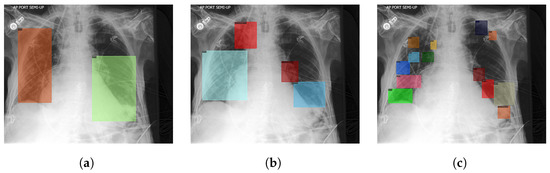

- To surpass the requirements of medical professionals and save a large amount of time required to annotate the COVID-19 lung lesion images, we developed our semi-self-supervised method. It leverages a prototype model from preliminary experiments (Teacher), which extracts the lung lesion features from pneumonia images, then helps us identify lung regions that potentially have lung lesions on unannotated COVID-19 CXR, in the form of pseudo-boxes. A novice annotator is supervised by these pseudo-boxes and then distills these boxes into the annotation data of COVID-19 CXR. Figure 1 illustrates our proposed method.